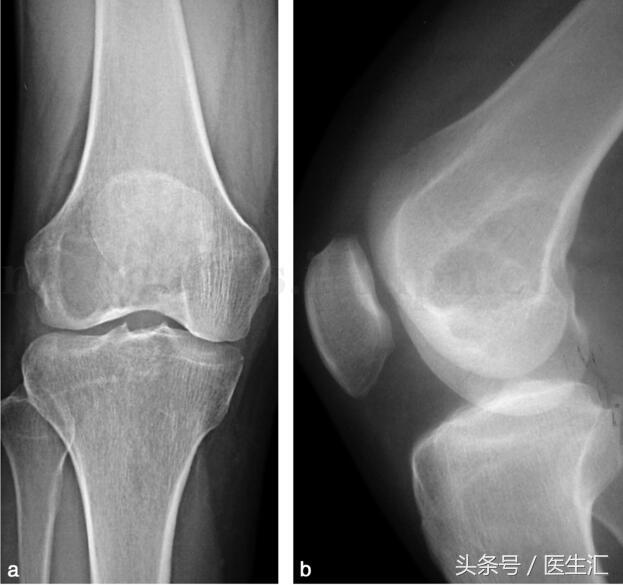

影像學(xué)檢查:X 線示右股骨遠(yuǎn)端骨端發(fā)生的一個(gè)偏心、基質(zhì)均勻、皮質(zhì)膨脹、皮質(zhì)無(wú)骨破壞、無(wú)骨膜反應(yīng)、無(wú)軟組織腫塊的溶骨性破壞(圖29‐1a,圖29‐1b)。CT 示右股骨遠(yuǎn)端骨端的溶骨性破壞,基質(zhì)均勻,注射造影劑后,病變強(qiáng)化,CT 值由強(qiáng)化前的40HU 增加到強(qiáng)化后的110HU(圖29‐2a~圖29‐2c)。

圖29‐1

a﹒右股骨下段外髁部溶骨性骨破壞(X 線正位片);b﹒右股骨下段外髁部溶骨性骨破壞(X 線側(cè)位片)

在影像學(xué)上,骨巨細(xì)胞瘤表現(xiàn)為骨端發(fā)病的地圖狀溶骨性破壞,偏心,皮質(zhì)膨脹,基質(zhì)均勻,邊界清楚,皮質(zhì)可有骨破壞,可有軟組織包塊。病灶內(nèi)偶有骨性間隔或假性骨間隔存在。